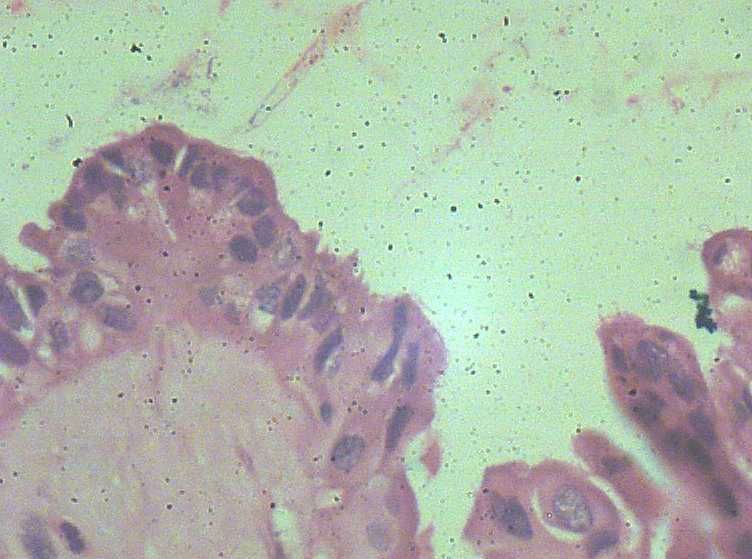

女,27岁,剖宫产术中见一侧卵巢一肿物。大体:椭圆形肿物大小3*2*1.5表面光滑,剖开内容为浅黄色胶状物,质均,囊内壁较光滑,部分见细小乳结构。

• 卵巢交界性浆液性囊腺瘤?图2

图2

那这例还真不好下诊断了 组织学已到了交界 但又不得不考虑妊娠的因素。这样的标准究竟是什么?本人感觉是个良性的 但组织学又到了交界 真不知道如何下诊断 要不下个 病变符合交界性?

有乳头的部位 基本都有取到了 。看来报个交界性不是问题了。谢谢各位老师的意见!